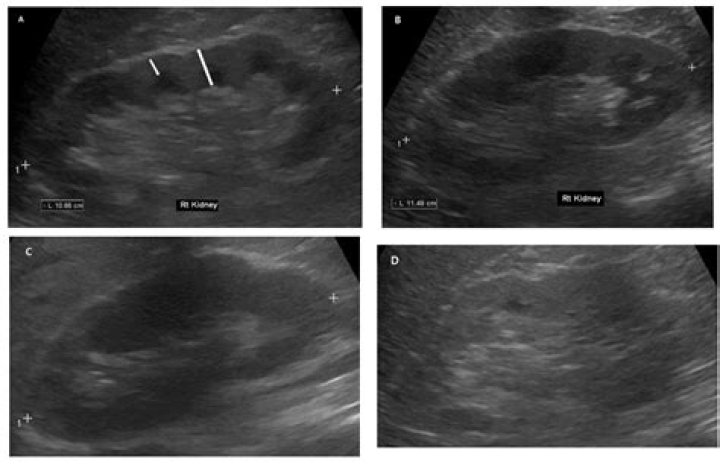

High resolution ultrasound of liver (A) shows diffusely altered